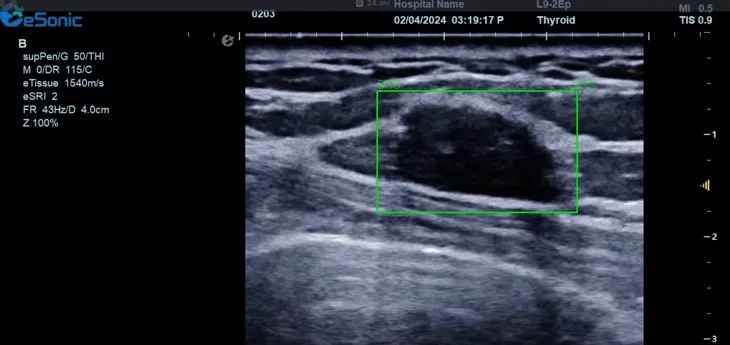

对于乳腺结节相关的自动检测功能,乳腺结节病灶检出率≥95%、良恶性分类灵敏度≥90%、良恶性分类特异度≥85%。